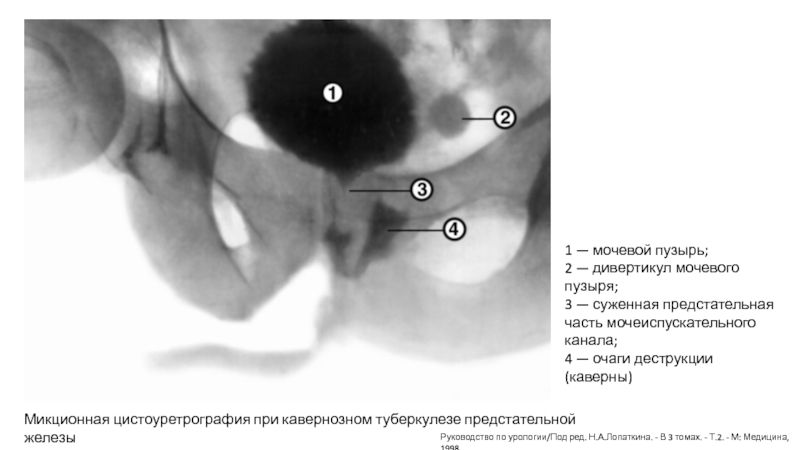

Слайд 10Микционная цистоуретрография при кавернозном туберкулезе предстательной железы

1 — мочевой пузырь;

2

— дивертикул мочевого пузыря;

3 — суженная предстательная часть мочеиспускательного

канала;

4 — очаги деструкции (каверны)

Руководство по урологии/Под ред. Н.А.Лопаткина. - В 3 томах. - Т.2. - М: Медицина, 1998